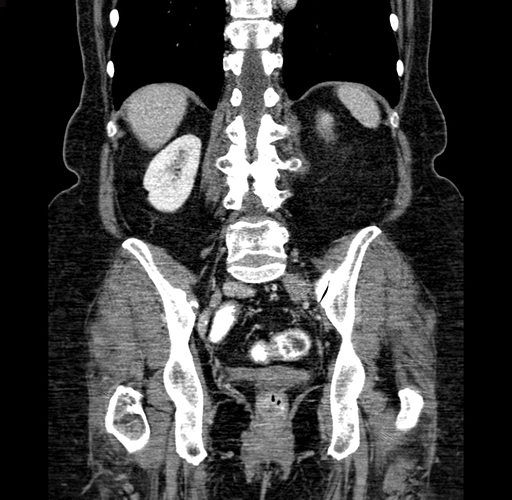

Pre-Chemo: Coronal Venous

Coronal Venous